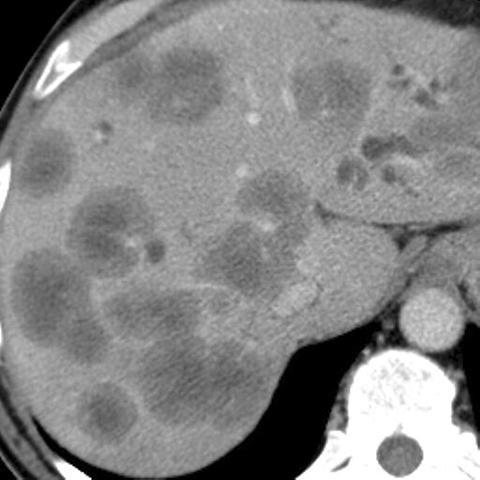

Liver metastases, CT ( axial ) [1 of 3]